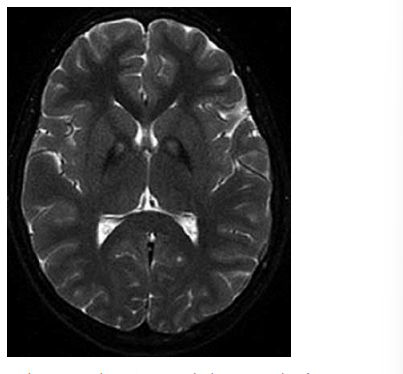

Menina de 9 anos de idade apresenta história progressiva de distonia, disartria e regressão cognitiva. A imagem por ressonância magnética de crânio revela o achado a seguir.

O gene mais provavelmente associado ao quadro é: